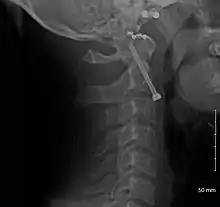

- A fracture of the base of the dens as seen on plain X-ray